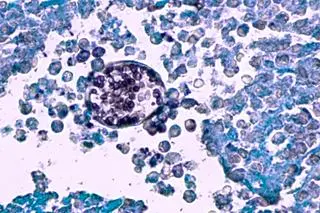

Coccidioides immitis pod mikroskopem

- Nasza analiza skupiała się na patogenach obecnych w płucach małych ssaków - donosi Paris Salazar-Hamm, autorka badania. - Odkryliśmy, że wiele przebadanych przez nas gryzoni (...) przenosiło grzyby, które mogą wywoływać choroby u człowieka, w tym kokcydioidomikozę. Ma ona podobne objawy do grypy i może stwarzać zagrożenie dla życia.

Wywołujące ją grzyby Coccidioides zostały znalezione w dużych ilościach przede wszystkim u zwierząt z rejonów, w których choroba ta występuje powszechnie. Naukowcy wykryli je jednak również w próbkach pochodzących z obszarów, gdzie dotychczas nie notowano obecności tych grzybów.